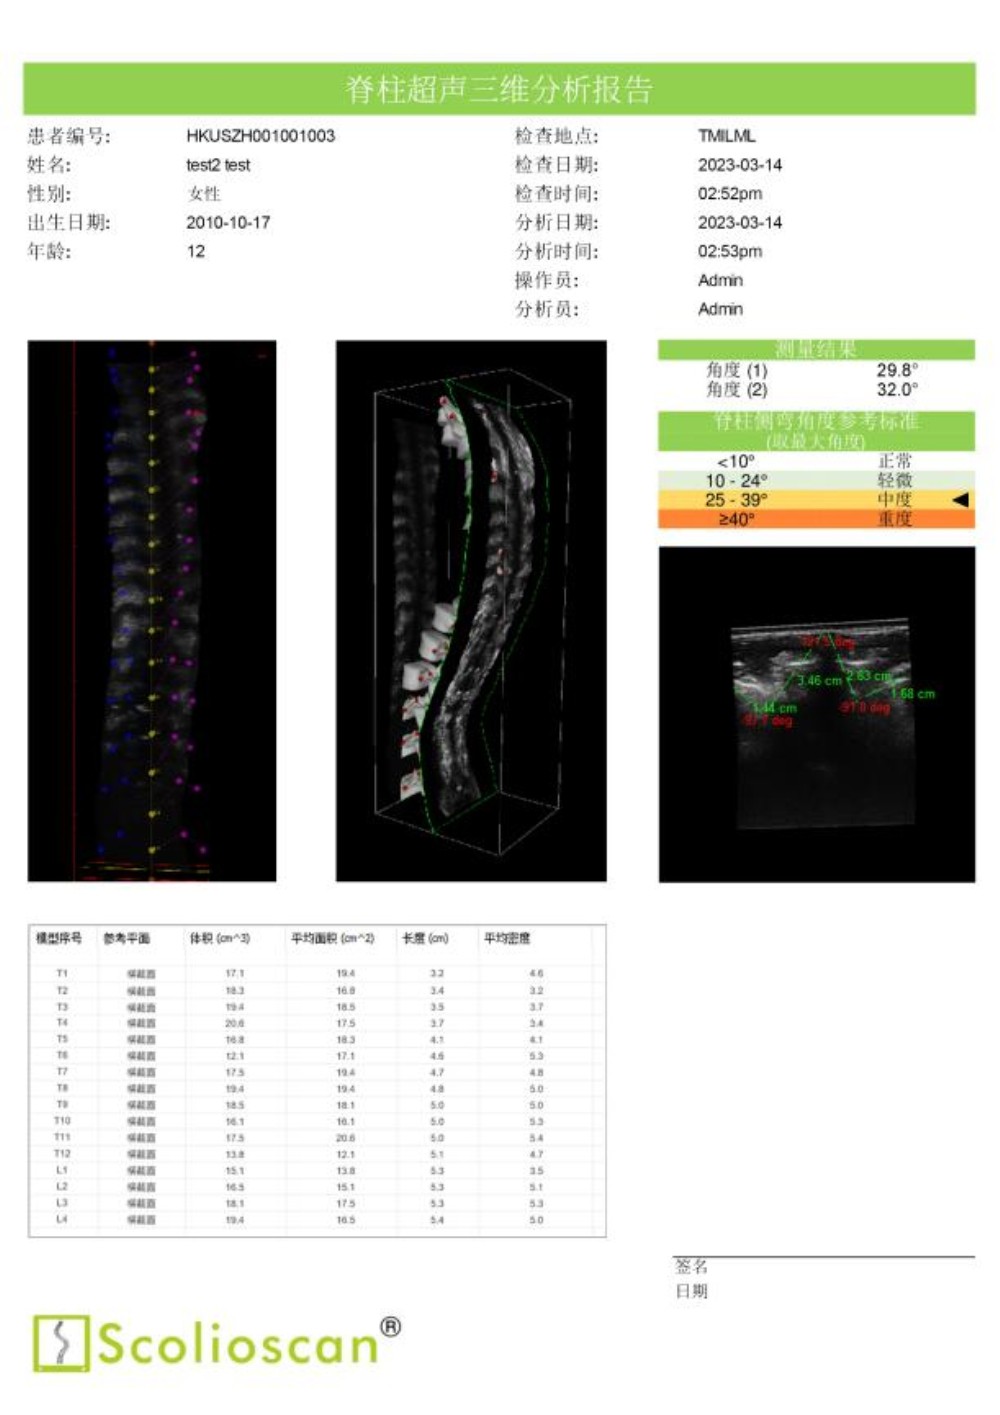

临床试验结果显示,Scolioscan®的测量结果与X光成像高度一致,线性相关度达到0.9464。使用Scolioscan®及早发现青少年的脊柱侧弯问题后,医生得以把握宝贵的黄金治疗时机,通过非手术方式有效控制和治愈疾病,实现早诊断、早治疗、早康复。

通过动态监测侧弯治疗情况,医生能有效帮助孩子选择适合的运动与锻炼方法。密切的超声监测有助于医生在疾病治疗的黄金期积极追踪病情和评估、调整治疗方案,根据脊柱的最新状况,第一时间采用体育运动、手法治疗、支具佩戴等保守疗法为患者矫正,有效减小脊柱侧弯度数。Scolioscan®提供的肌骨三维分析还可以协助医生以关节—肌肉—神经三维度为整体,全面进行脊柱侧弯的综合康复治疗。

内蒙古自治区首台“Scolioscan®无辐射三维超声脊柱侧弯评估系统”成功引入我院,可广泛应用于脊柱侧弯筛查、诊断、病情跟踪和预测以及非手术治疗阶段对治疗结果的可视化反馈和评价等多个领域,为广大儿童青少年提供精准度媲美X光的无辐射、安全的脊柱侧弯评估方案,帮助患有脊柱侧弯的孩子早发现、早干预、早康复,竖起脊梁健康成长。